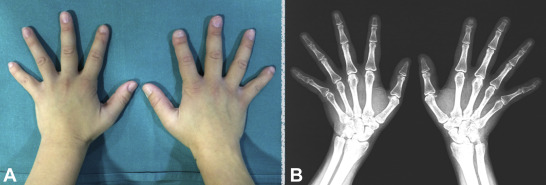

More than likely something called Acro-Osteolysis has resulted in odd finger tips.

Acro-Osteolysis: Acro-osteolysis is basically the fancy medical term for when the tips of your fingers or toes start to lose bone. Imagine if the very ends of your bones, like where your nails sit, slowly start to disappear or melt away. That’s what’s happening with acro-osteolysis. It makes those areas thinner and can even make your fingers or toes look shorter over time. At first, It’s not painful in itself. It can lead to other problems because the bone structure isn’t as strong or normal as it should be. Partial dislocations are common as the joints degenerate over time. Once the connective tissues have nothing strong enough to hold them they get very painful and eventually pull away from the joint. This leads to further loss of strength and dexterity which leads to more damages.